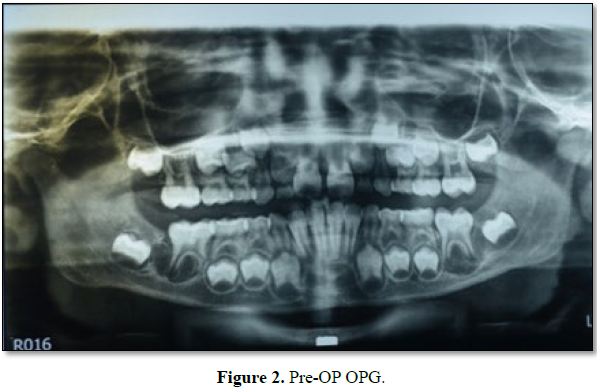

Patient has no relevant past medical or dental history. On oral examination

nothing suspicious was found. Patient had good oral hygiene. Patient was

advised for OPG. OPG revealed presence of radiolucency wrt to 36 and 46.

Patient complained swelling only but OPG revealed similar lesion on the other

side also which was not known to patient or parents as it was asymptomatic (Figure

2).